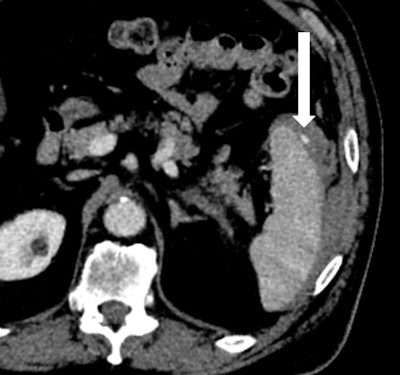

After initial resuscitation and focused assessment with sonography in trauma (FAST), he underwent a CT of the chest, abdomen, and pelvis that revealed a 1.4-cm grade III splenic laceration near the anterior lip associated with a focus of contrast extravasation. The exam also revealed an associated subcapsular hematoma larger than 50% of the surface area of the spleen, with hemorrhage tracking along the left paracolic gutter into the pelvis (figures 1A and 1B). The pancreas appeared unremarkable on this CT (figure 2).

Figure 2: Axial view of CT of the abdomen demonstrates unremarkable appearance of the pancreas on arrival (white arrow).Splenic arteriogram demonstrated parenchymal injury and active extravasation, which corresponded with the CT, with identifiable contrast extravasation (figure 3A). In a location distal to the dorsal pancreatic artery, SAE was performed utilizing 0.035- and 0.018-inch coils.